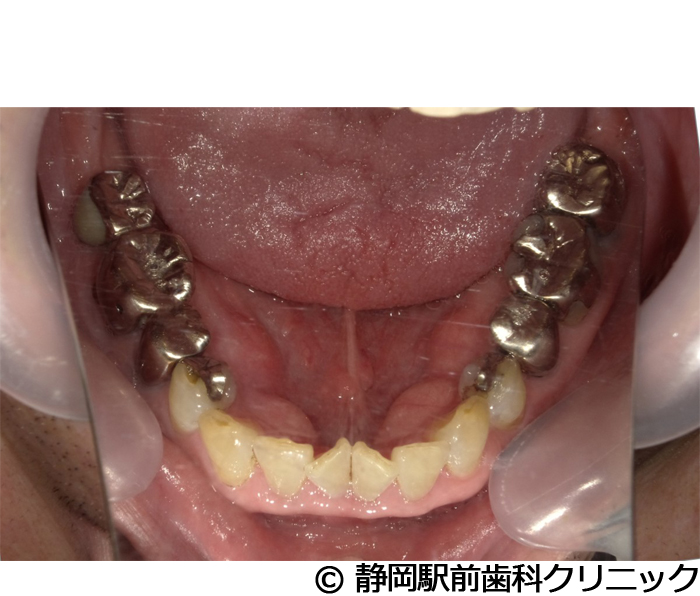

【症例5】全顎的インプラントとセラミックによる審美補綴

- 治療前

- 治療後

- 治療名

- 全顎的インプラントとセラミックによる審美補綴

- 費用

- 1,800,000円(税込)

- 期間

- 1年6ヵ月

治療内容

患者様の症状

全体的に歯がないため、噛めない。インプラント治療希望。

治療方法

全体的に残根は抜歯を行い、術前にCTを撮影し緻密に治療計画を立てた。インプラント埋入はブロックごとに行い、噛み合わせの調整を重ねた後、人工歯を被せて咬合と審美の回復を行いました。

治療結果

しっかり奥歯で食べ物を噛み切ることができるようになり、何でも食べることができるようになったと喜んでいただくことができました。口元を気にせずに笑うこともできるようになり、見た目もキレイになったとご満足いただけました。

※治療結果は個人差があります。

治療を行う上での注意点(リスク・副作用)

術後は、出血、腫れ、痛みなどが出る可能性があります。